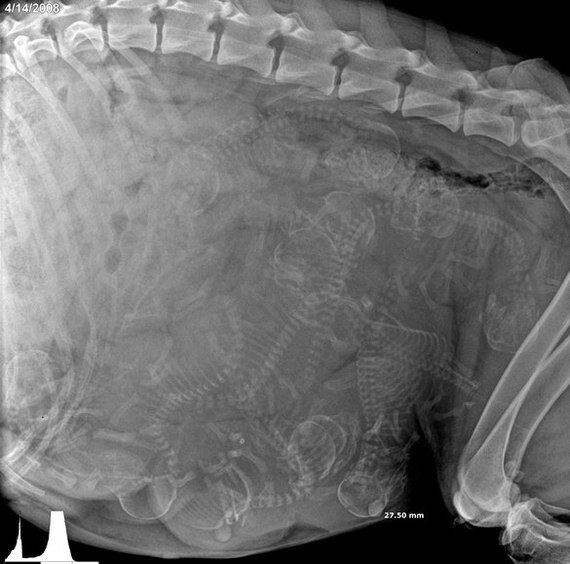

Фото: Рентген беременной собаки

Может я ненормальная, но мне это кажется очень милым. Просто посмотрите, как это прекрасно. Удивительно, как они там все умещаются внутри и не калечат друг друга. Рентген позволяет узнать количество щенков и размеры таза собаки, чтобы роды прошли удачно. А вот еще рентген кошки. Котята, кажется, лежат еще плотнее: